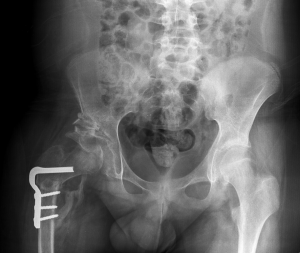

Se invece si è in presenza di una significativa ossificazione, è necessario eseguire anche una radiografia, dal momento che non è più possibile eseguire l’ecografia.

Trattamenti chirurgici

Da 6 mesi a 2 anni e oltre

Se la lussazione è più grave e la “riduzione chiusa” non ha avuto successo (qualora invece l’anca non possa essere riposizionata manualmente), è necessario intervenire con una procedura chirurgica chiamata “riduzione aperta”. Si tratta di un intervento vero e proprio in cui il chirurgo ispeziona l’articolazione e:

- rimuove eventuali tessuti molli anomali che tengono l’anca al di fuori dell’acetabolo

- tende legamenti e capsula che si sono allentati

- allenta muscoli che si sono contratti

Dopo l’intervento chirurgico potrebbe essere necessario trattare il paziente con un gesso per mantenere l’anca nella posizione corretta all’interno dell’acetabolo.

Nei casi di lussazione più grave potrebbe essere necessario, in pazienti più grandi, effettuare un intervento chirurgico di ricostruzione dell’acetabolo e riposizionamento della testa del femore. Questo spiega l’importanza di una diagnosi precoce che permette un trattamento molto meno invasivo.